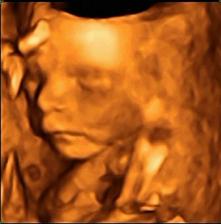

......bude to klučík.....